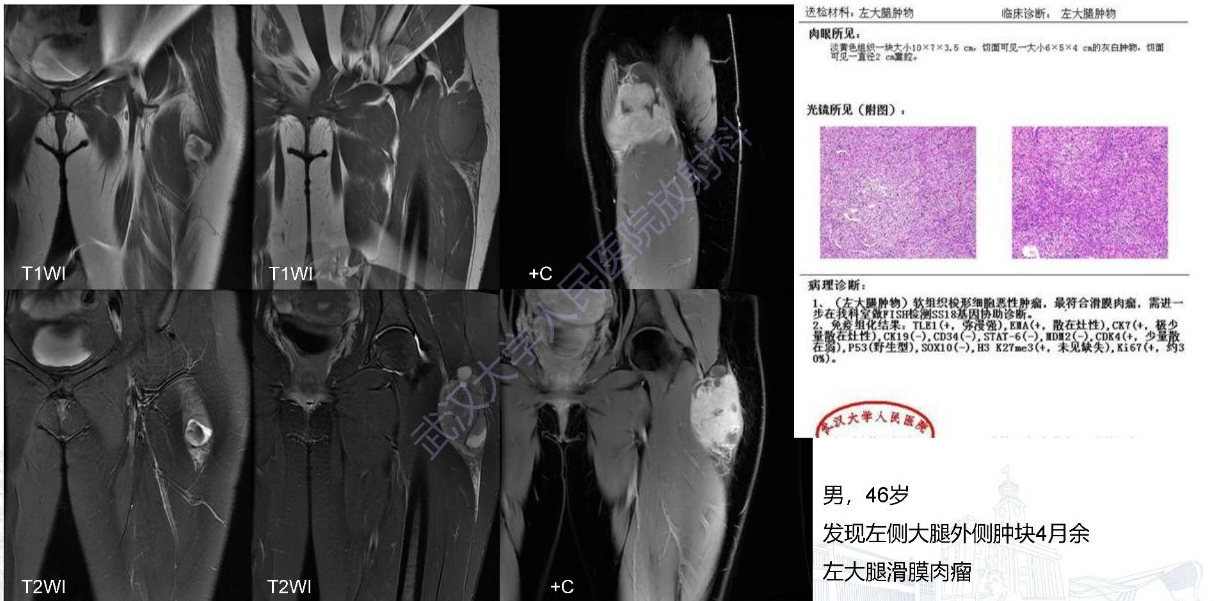

1.滑膜肉瘤: 好发于青壮年(15-35岁),多见于四肢的深部软组织,以下肢多见,一般邻近关节,易包绕骨骼生长,可侵犯和侵蚀邻近骨质。T2WI肿瘤有时亦可见线状低信号分隔,病理证实为肿瘤内胶原纤维或瘤结节内纤维组织T2WI信号混杂,表现为以高信号为主的混杂信号,可有低、等、高三种信号同时存在,即“三信号征”。增强扫描呈明显不均匀强化,实性成分强化,坏死、囊变、血肿不强化,而EMC可表现为分隔样强化。